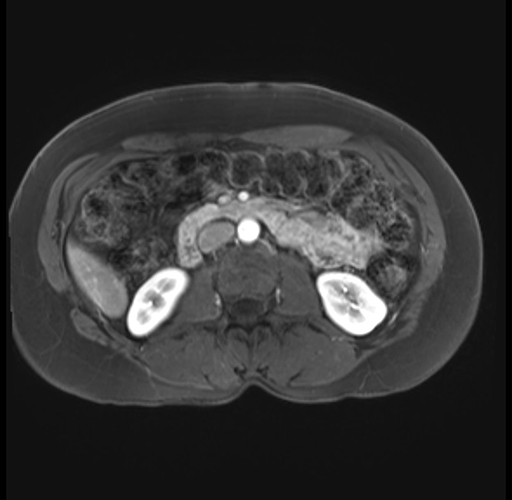

Imaging Analysis

Look through the patient's CT scan to identify any areas of concern for the necessary procedure.

Based on your CT findings, which issue(s) are present and would give reason for "planned slowing down moment(s)" in this case?